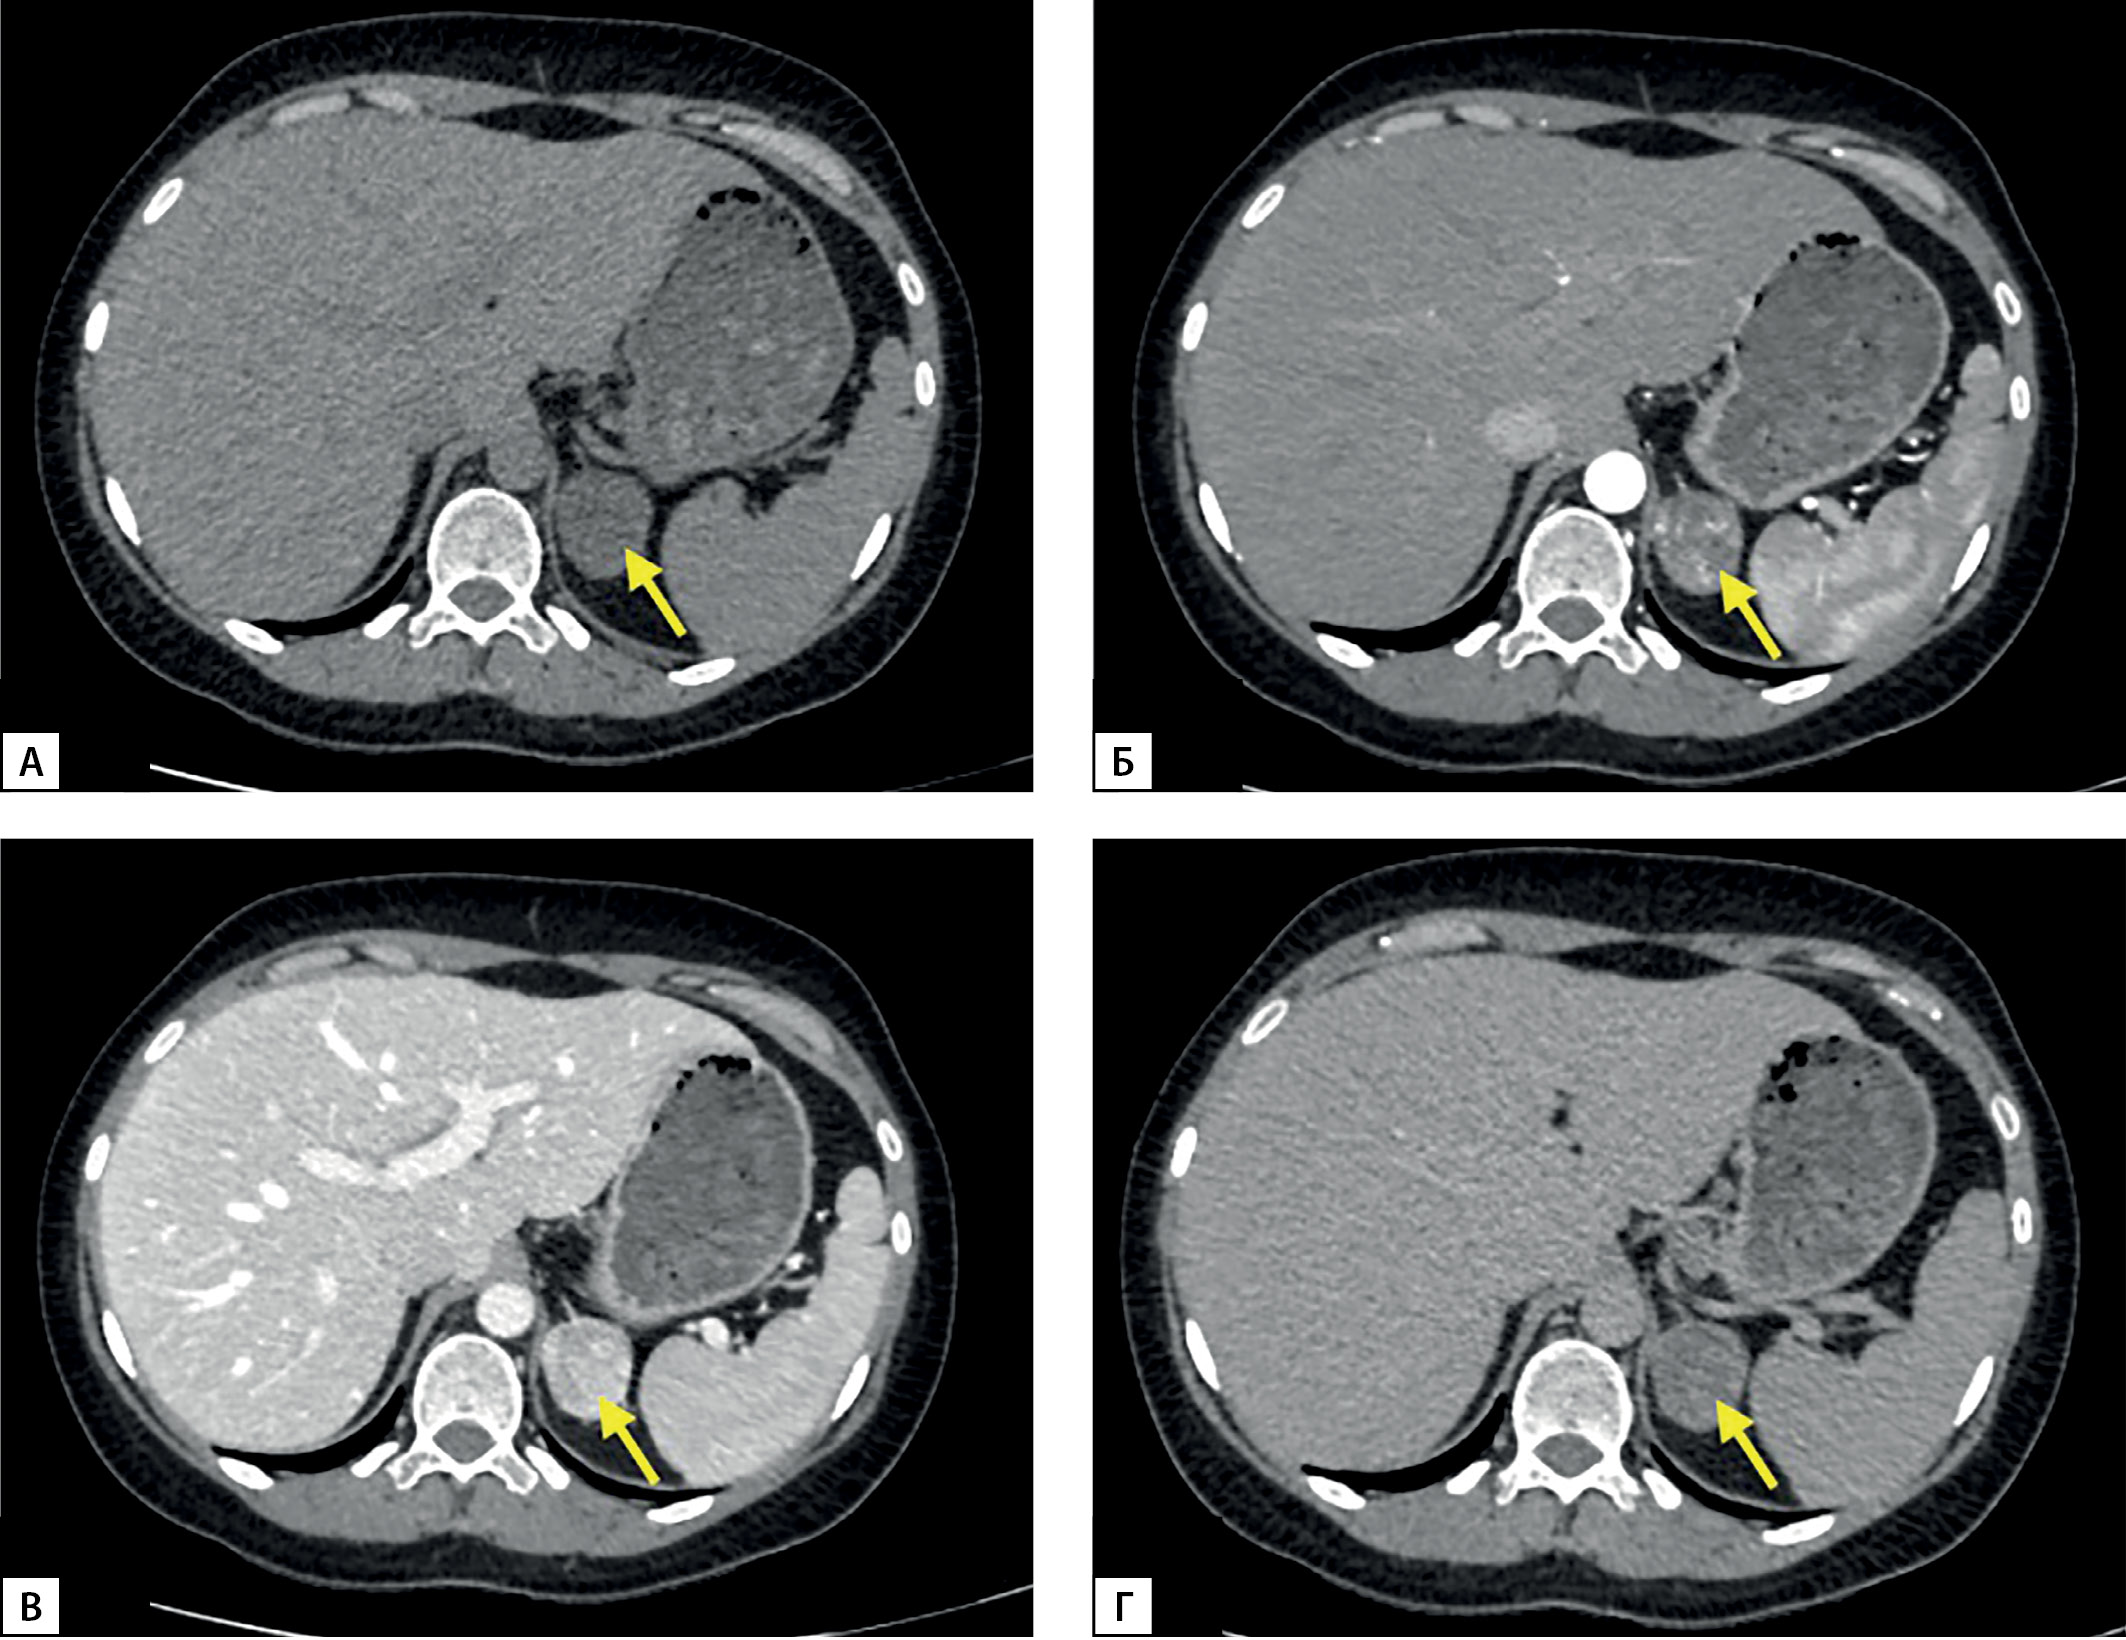

По данным МСКТ визуализировано образование левого надпочечника с четкими ровными контурами размерами 3,5х3,4х3,2 см, плотностью в нативную фазу от 12 HU до 17 HU, с наличием многочисленных сосудов в структуре, при контрастном усилении накапливает контраст, плотность по фазам 70–160–75 HU (артериальная-венозная-отсроченная) (рис. 1). Коэффициент абсолютного вымывания контрастного вещества — 59%, относительного — 53%. КТ-характеристики соответствуют злокачественному фенотипу.

Рисунок 1. МСКТ надпочечников: А — нативная фаза; Б — артериальная фаза; В — венозная фаза; Г — отсроченная фаза.

Figure 1. MSCT scan of adrenal glands: A — native phase; B — arterial phase; C — venous phase; D — delayed phase.

1. Рисунок 1. МСКТ надпочечников: А — нативная фаза; Б — артериальная фаза; В — венозная фаза; Г — отсроченная фаза.